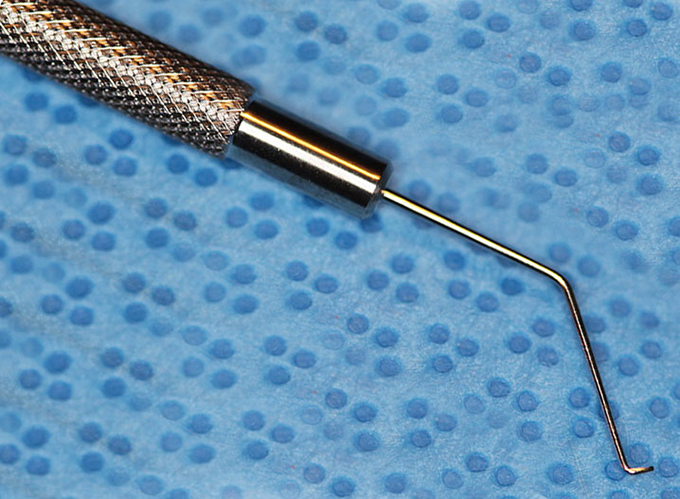

Kuglen Hook, straight, round handle

Kuglen

Catalog: Katena K3-5522

Typical Use(s): Position IOL and haptics; Fix eye with paracentesis; Retrieve suture from AC

Kuglen Hook, straight, round handle (Enlarged)

Kuglen

Catalog: Katena K3-5522

Typical Use(s): Position IOL and haptics; Fix eye with paracentesis; Retrieve suture from AC